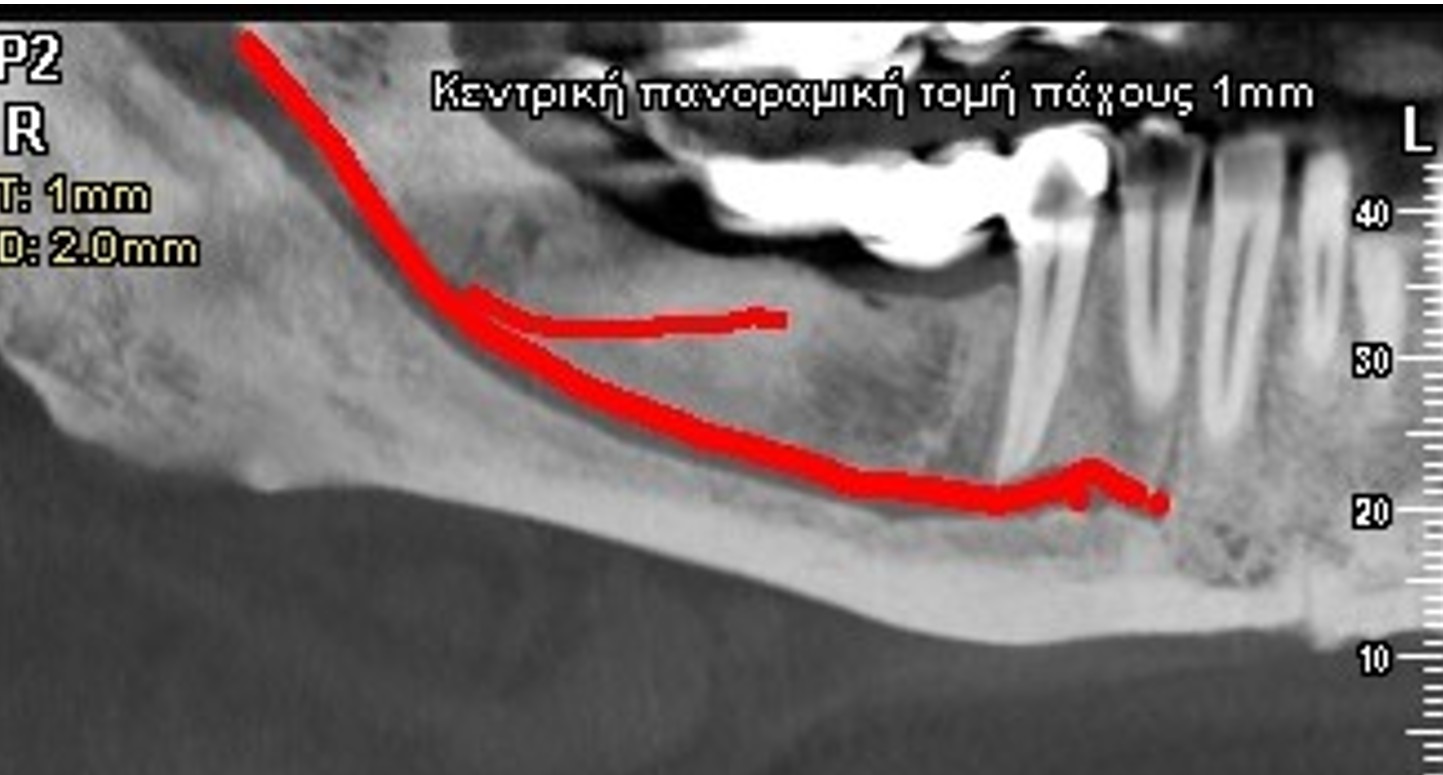

Η Ογκομετρική Υπολογιστική Τομογραφία μοιάζει με την ιατρική αξονική τομογραφία, υπερτερεί όμως αυτής, λόγω της μειωμένης δόσης της ακτινοβολίας που δέχεται ο εξεταζόμενος από τη δυνατότητα ταυτόχρονης λήψης της άνω και κάτω γνάθου, καθώς και της δυνατότητας επικέντρωσης της δέσμης ακτινοβολίας σε μικρή περιοχή της γνάθου. Παρέχει υψηλή ευκρίνεια και τη δυνατότητα πραγματοποίησης ακριβών μετρήσεων για πολλά θεραπευτικά σχέδια. Η δυνατότητα επιλογής πολλαπλών πεδίων ακτινοβόλησης από το μηχάνημά μας παρέχει αξιόπιστες εφαρμογές και για απαιτητικά οδοντιατρικά πεδία όπως ενδοδοντία, περιοδοντολογία κ.λ.π.

Η χρησιμότητα της Οδοντιατρικής Υπολογιστικής Τομογραφίας (dental scan) αναδεικνύεται μετά την επεξεργασία των εικόνων, εργασία που απαιτεί γνώση και εμπειρία. Έτσι η εξέταση εξατομικεύεται για κάθε ασθενή ανάλογα με το διαγνωστικό πρόβλημα που αντιμετωπίζεται.

Κατά την επεξεργασία των εικόνων, που προκύπτουν από την ανασύνθεση της Οδοντιατρικής Υπολογιστικής Τομογραφίας σημειώνονται στις εικόνες ανατομικά στοιχεία, γίνονται μετρήσεις και σημειώνεται και η παθολογία όταν απαιτείται.